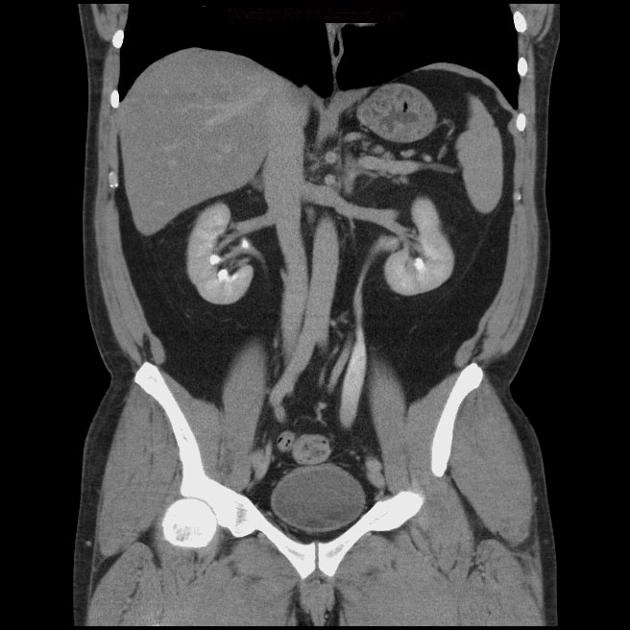

Hẹp niệu quản (Ureteral stricture)